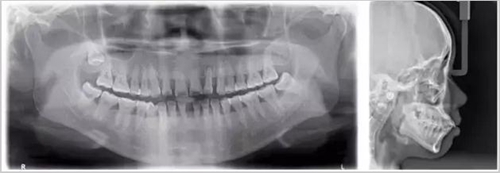

從上圖中可以知道除了外層的一點牙釉質(zhì),牙齒里面出了問題,肉眼是無法觀察到的。牙醫(yī)不長透視眼當(dāng)然不能透過現(xiàn)象看到牙齒本質(zhì)嘍。因此,為了對牙齒進行全面的了解,拍個牙片還是很有必要的。